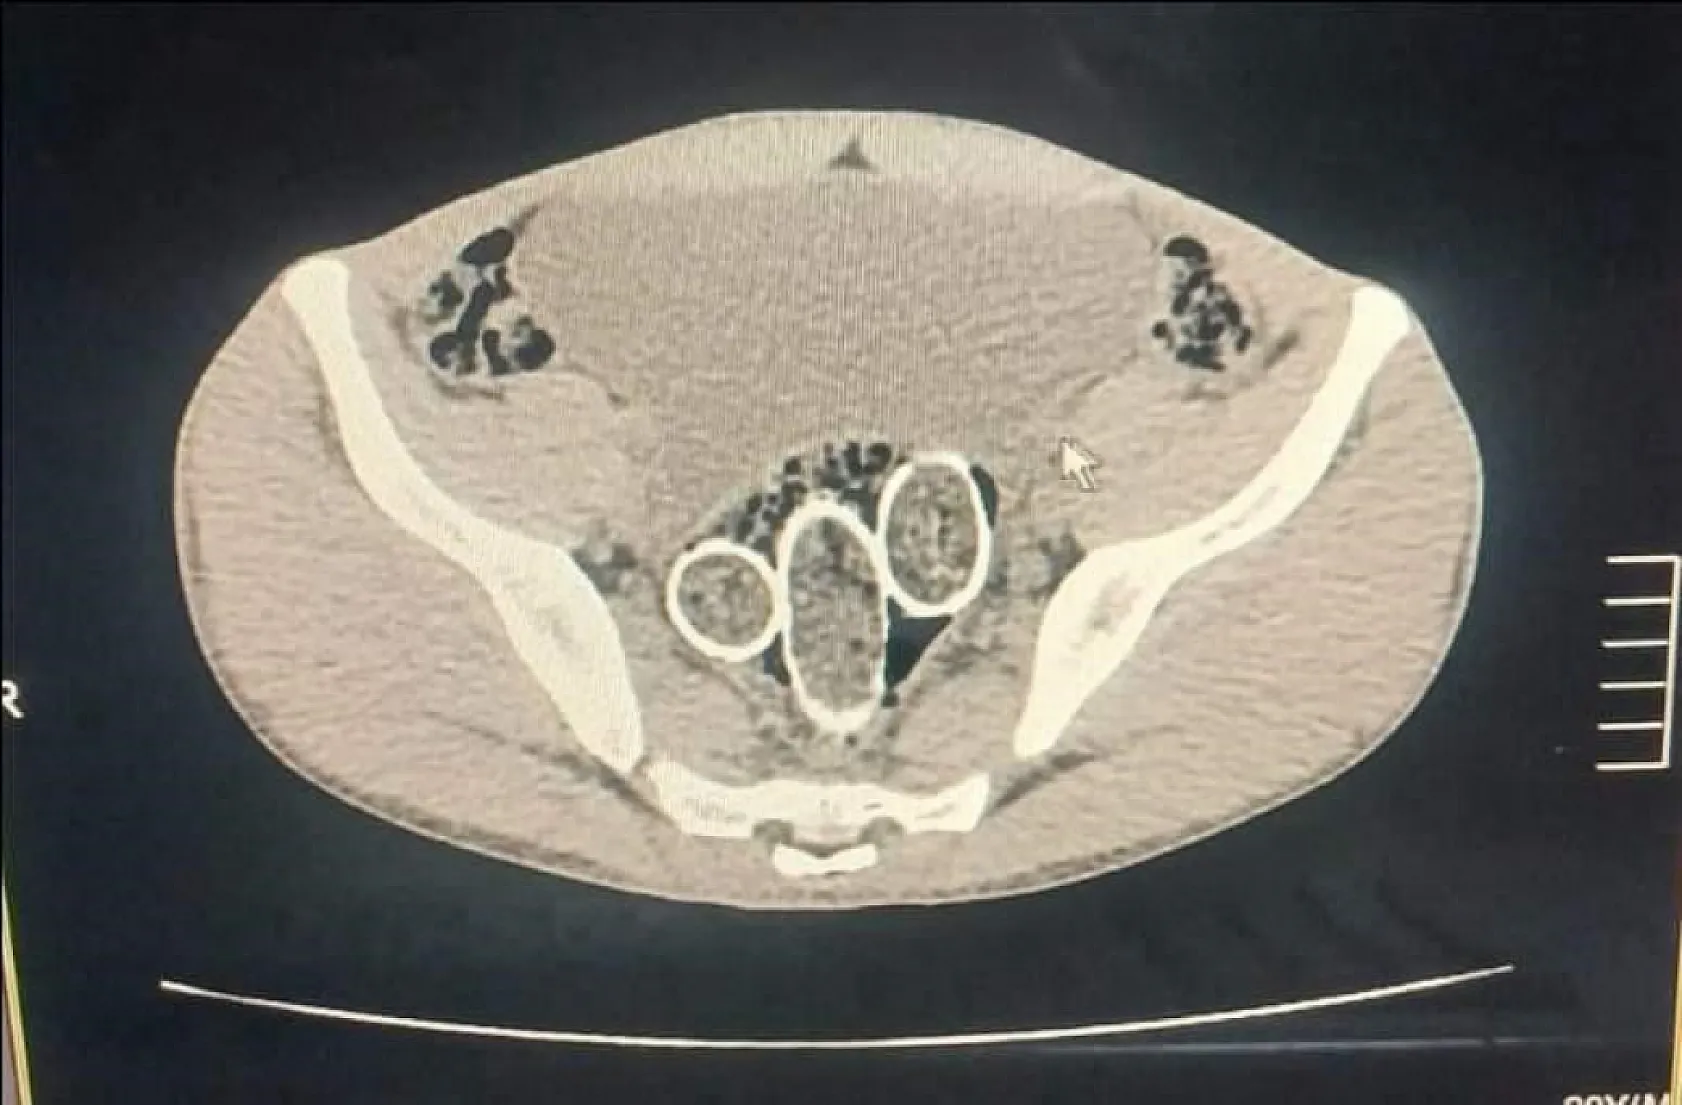

Polisin düzenlediği uyuşturucu operasyonunda gözaltına alınan 5 şüpheliden 2'sinin yapılan iç beden muayenesinde rahim ve mideye saklanmış 320 gram uyuşturucu madde ele geçirildi.

Denizli İl Emniyet Müdürlüğü Narkotik Suçlarla Mücadele Şube Müdürlüğü ekiplerince, uyuşturucu ticaret yapan şahıs veya organizasyonların yakalanmasına yönelik operasyon düzenlendi. Düzenlenen eş zamanlı operasyonlarda 5 şüpheli şahıs yakalanırken, iki şahsın yaptırılan iç beden muayenesinde ve kullandıkları iki araçta yapılan incelemelerde rahimde ve midede uyuşturucu madde tespit edildi.